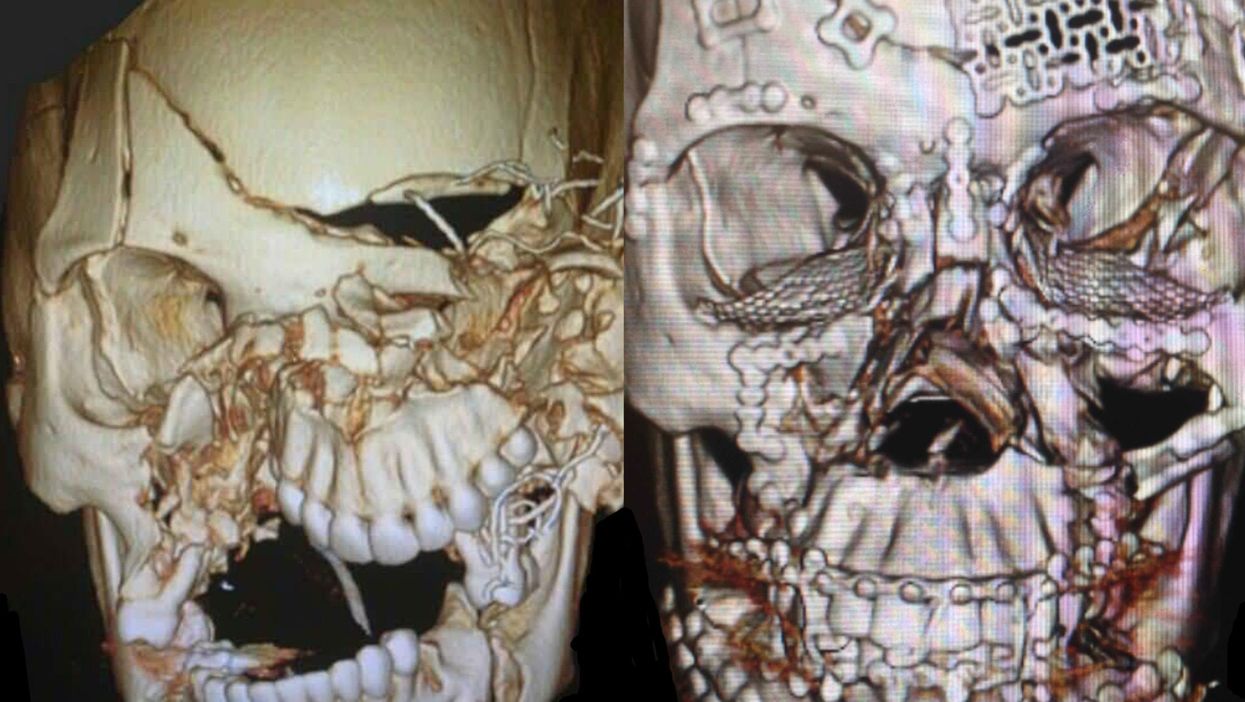

The CT scans from a 25-year-old woman show the dramatic damage to the skull after she was involved in a serious car crash, followed by the end result after an eight hour reconstructive procedure.

A trauma work-up revealed a traumatic brain injury with intracranial hemorrhage, a traumatic eye injury requiring enucleation, and extensive facial fractures.

This CT shows her completed facial reconstruction. Thanks to a dedicated multidisciplinary team, the patient is now ambulatory and recovering well.